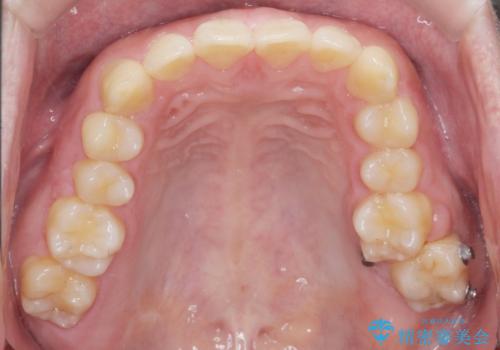

左上の奥歯がシザーバイトがありワイヤーで部分的な矯正を行い、シザーバイトを改善した後にインビザラインで全体的な矯正治療を行いました。

シザーバイトは歯と歯が噛み合っていないのでしっかり噛むように処置をする必要があります。